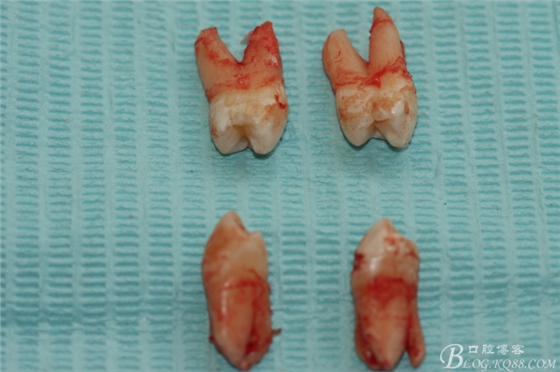

患者:江某某、男、14歲。因正畸治療需要拔除上下頜四顆第一前磨牙。按醫(yī)囑,局麻下拔除四顆第一前磨牙。牙齒拔除后發(fā)現(xiàn)四顆牙齒均為三個(gè)根,頰側(cè)兩根,腭側(cè)一個(gè)根。上頜第一前磨牙偶見(jiàn)三根。下頜第一前磨牙左右兩側(cè)均為三根,實(shí)屬罕見(jiàn)。發(fā)圖片,與同仁共勉。

7.四顆離體上下頜第一前磨牙牙根形態(tài)